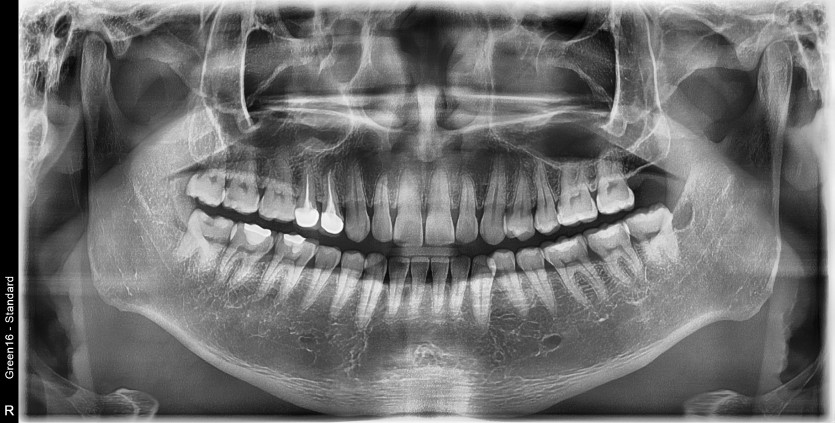

#18,48 사랑니 발치

구강 외과 전문의가 당일 발치했습니다.